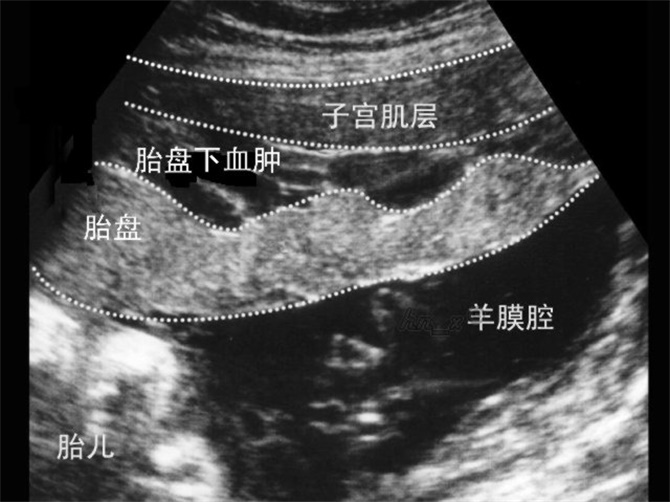

胎盤早剝超聲診斷

胎盤早剝胎盤血腫

胎盤早剝血腫超聲